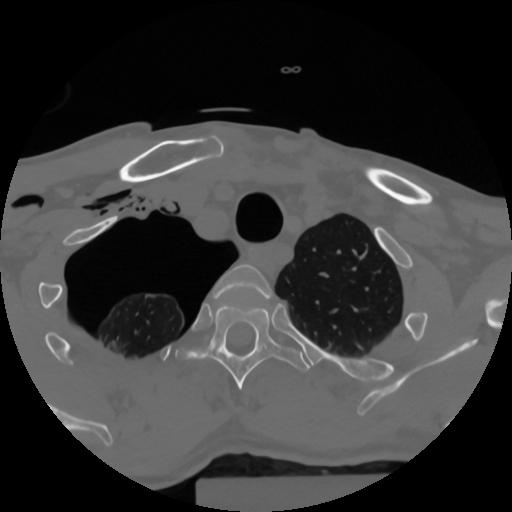

12 P.BLANDAS,,Vol,0.5,P.BLANDAS,,